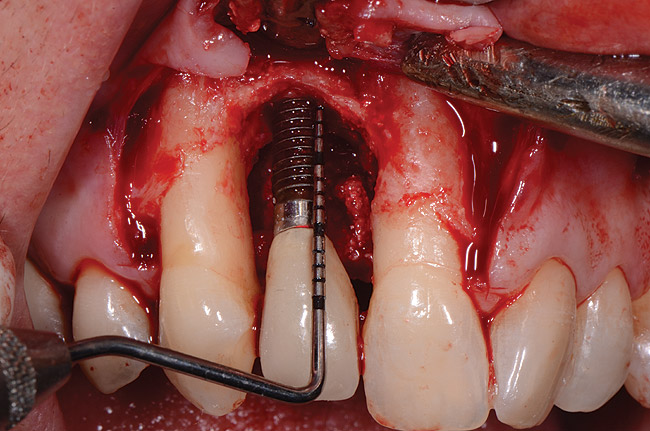

A 46-year-old man with an unremarkable medical history was referred for evaluation and treatment of the maxillary right central incisor implant. The implant, which had been placed 6 years prior, had never caused any problems until recently, when the patient noted both swelling and soreness at the site. Following 10 days of amoxicillin 500 mg tid, purulence was still present upon palpation of the tissue, and the patient was referred for consultation (Figure 6). Probing attachment loss of 10 mm on the distal aspect and 5 mm on the mesial were measured around the implant. Bone loss was advanced on the periapical radiograph at both the mesial and distal aspects of the hydroxyapatite-coated implant (Figure 7). Full-thickness facial and lingual flaps were reflected to access the implant and surrounding bone, with care taken to preserve the papilla. The defects around the implant on the mesial and distal were 1-wall, and bone loss was present on the direct facial and palatal aspects as well (Figure 8). The surface of the implant was decontaminated, followed by application of enamel matrix derivative. The lesion was filled with freeze-dried bone allograft (Figure 9). The graft-biologic was covered by a flowable polymer barrier (Figure 10). The flaps were coronally advanced and secured with monofilament sutures (Figure 11). The patient was prescribed amoxicillin with clavulanic acid and an oral rinse of 0.12% chlorhexidine during the post-operative period. The healing progressed uneventfully, achieving both a favorable soft-tissue profile and substantial bone fill, as determined radiographically. These results were stable for 7 years (Figure 12 and Figure 13).

Figure 8  Flap reflection revealed circumferential bone loss.

Figure 8